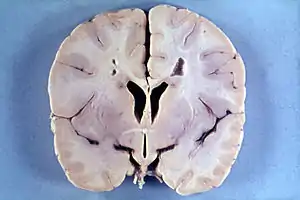

Many people with abnormally large heads or large skulls are healthy, but macrocephaly may be pathological. Pathologic macrocephaly may be due to megalencephaly (enlarged brain), hydrocephalus (abnormally increased cerebrospinal fluid), cranial hyperostosis (bone overgrowth), and other conditions. Pathologic macrocephaly is called "syndromic", when it is associated with any other noteworthy condition, and "nonsyndromic" otherwise. Pathologic macrocephaly may be caused by congenital anatomic abnormalities, genetic conditions, or by environmental events.[2]

Macrocephaly is customarily diagnosed if head circumference is greater than two standard deviations (SDs) above the mean.[9] Relative macrocephaly occurs if the measure is less than two SDs above the mean, but is disproportionately above that when ethnicity and stature are considered. Diagnosis can be determined in utero or can be determined within 18–24 months after birth in some cases where head circumference tends to stabilize in infants.[10] Diagnosis in infants includes measuring the circumference of the child's head and comparing how significant it falls above the 97.5 percentile of children similar to their demographic. If falling above the 97.5th percentile then the patient will be checked to determine whether there is any intracranial pressure present and whether or not immediate surgery is needed.[11] If immediate surgery is not needed then further testing will be done to determine whether the patient has either macrocephaly or benign macrocephaly.

Treatment varies depending on whether or not it occurs with other medical conditions in the child and where cerebrospinal fluid is present.[10] If benign and found between the brain and skull then no surgery is needed.[10][12] If excess fluid is found between the ventricle spaces in the brain then surgery will be needed.[12]